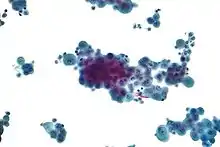

4. Cytopathology to identify cancer cells, but may also identify some infective organisms

When a pleural effusion has been determined to be exudative, additional evaluation is needed to determine its cause, and amylase, glucose, pH and cell counts should be measured.